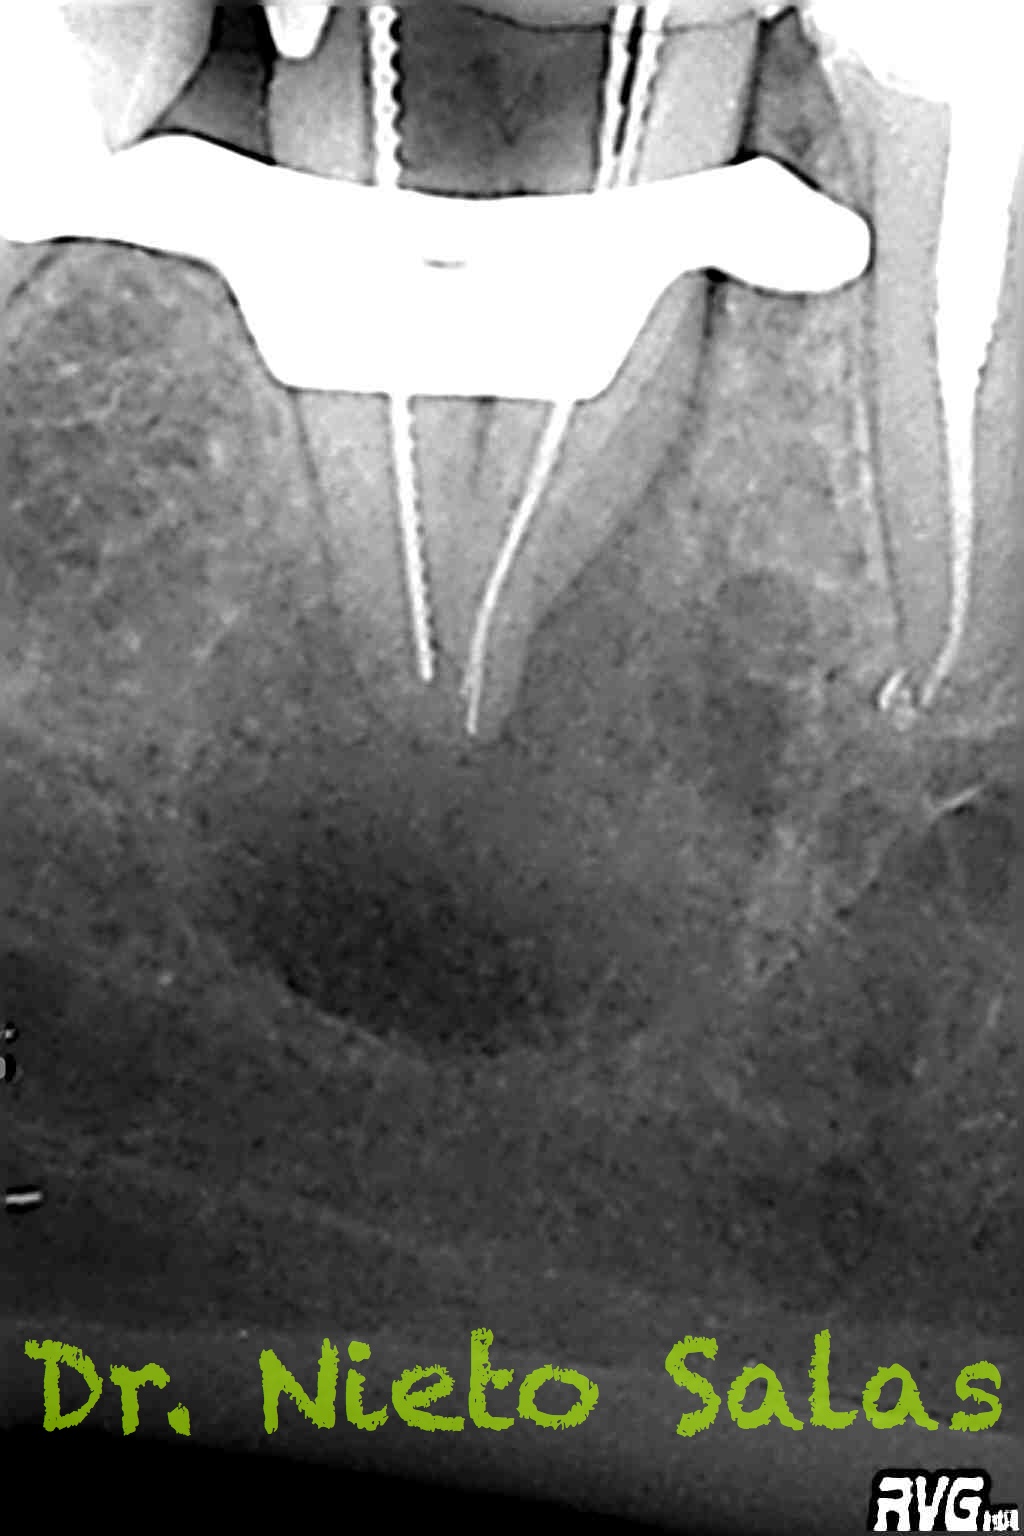

Una vez que tenemos todo preparado, se trata de un tratamiento de endodoncia convencional, con lo que seguiremos los pasos de limpieza, conformación y sellado del sistema de conductos.

Usamos técnica de obturación por ola continua de Buchanan modificada y hacemos un backfilling con gutapercha inyectada.

Presentaba un sistema de conductos en el que el conducto distal era acintado y los mesiales podían unirse después de instrumentarlos.

Me gusta ser conservador con los diámetros apicales, para deformarlos lo menos posible. En este caso no fue así por la anatomía que presentaba, adapté bien los conos maestros con un diámetro más o menos 45 en el conducto distal(recuerda que era acintado con lo que no es posible un único cono apical) y 30 los mesiales.